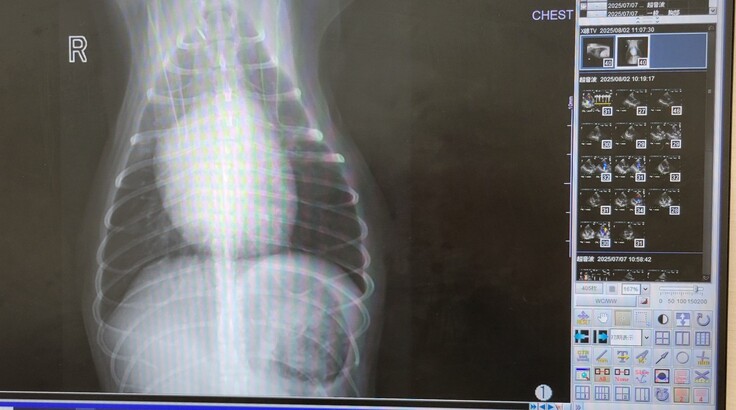

退院後1カ月の検診

本日は、ぷらむが退院してから約1か月後の検診に行ってきました。

結論としては、経過良好だったので、一安心です。

そして、かねてから心配であった咳の症状については、なんとレントゲン・エコー検査共に悪い部分が見当たらず問題なさそうで、手術時に横隔神経が一部麻痺となった部分の気管支に原因があると想定し、新たに気管支拡張の薬をいただき、経過観察することとなりました。

疑わしき影・モヤはありませんでした。

なにはともあれ肺水腫の再発ではなかったことに一安心です。